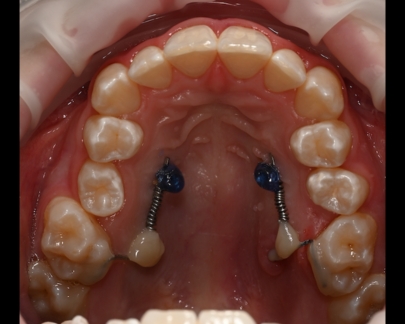

Mini implantul ortodontic este un dispozitiv mic din titan sau aliaj de titan care este utilizat pe perioada tratamentului ortodontic pentru a oferi ancorare suplimentară atunci când este necesară aplicarea unor forțe ortodontice mai complexe.

Acesta este inserat în osul alveolar, iar procedura de inserție este nedureroasă și efectuată sub anestezie locală.

![]() | ![]() | ![]() |